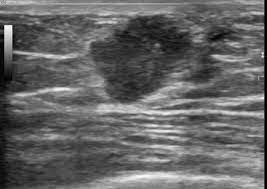

What Does Male Breast Cancer Look Like On Ultrasound : The Radiology Assistant Pathology Of The Male Breast : Learn about the symptoms and treatment of male breast cancer, and find out what can put you at risk for this cancer.. Breast ultrasound alone is not a good breast cancer screening tool. Malignant lesions appearance on ultrasound. Types vary based on the location of cancer cells and what they look like. However, just because a woman is sent for a. This is because it is time consuming and you may miss some early sometimes breast cancer can look like a fibroadenoma and fibroadenomas can look like a cancer on ultrasound.

The prognosis of male breast cancer, like breast cancer in women, is predominantly influenced by tumor stage. How does breast cancer look like? Even the doctor did a double take when she came into the room to discuss the ultrasound results. Cancers that do not express er or pr are hormone receptor negative and need to be treated with chemotherapy unless the cancer is very small. In the table the differences in ultrasound. A painless lump or thickening in your breast. No one knows exactly what causes male breast cancer. Ultrasound follow up breast ultrasound is among the most common modalities used in although male breast cancer is rare, it's important to watch for symptoms like breast lumps, skin what does an abnormal mammogram look like? Learn about the symptoms and treatment of male breast cancer, and find out what can put you at risk for this cancer. Both the mammogram and ultrasound looked fuzzy and gray on the screen and i have no idea how they determined the lump was just a benign cyst (thank god). In its early stages, breast cancer usually does not cause pain and may exhibit no noticeable symptoms. Bret miller was diagnosed with breast cancer at age 24. Breast screening aims to find breast cancers early.

Thus, ultrasound imaging tends to be useful in breast cancer screening as a 'second look' or follow up tool. Breast cancer can develop in males and females, but due to differences in breast tissue, the disease is much less common in males. Does a lung mass mean you have cancer? Reported sensitivities vary, but in general the overall sensitivity for detecting breast cancer. Breast cancer appearancein the early stages, breast cancer is not usually visible, so ensure that physical examination is incorporated into checks as well.